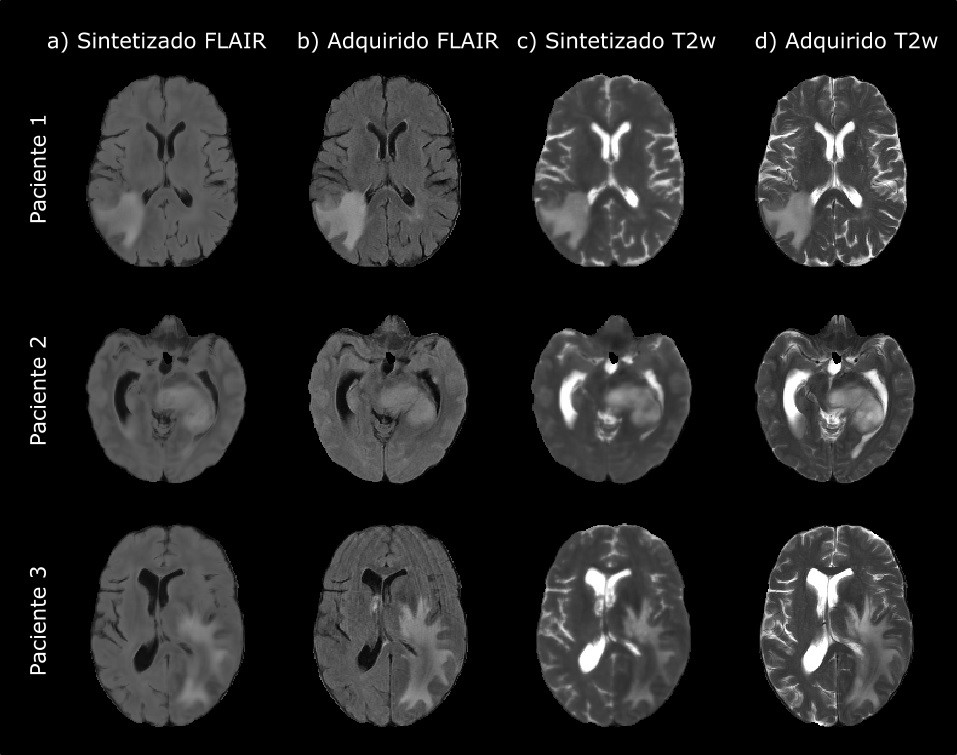

Fruto de este trabajo conjunto es la investigación llevada a cabo por Elisa Moya y Rafael Navarro, dos investigadores predoctorales de la UVa, que han conseguido generar gracias a la Inteligencia Artificial imágenes sintéticas que podrán utilizarse junto a las que se crean en una resonancia magnética, en el diagnóstico y la predicción del tratamiento del glioblastoma, el tipo más común de tumor cerebral maligno.

Esta nueva técnica desarrollada por los investigadores de la UVa, se suma a las que se utilizan actualmente en el diagnóstico, pronóstico y respuesta terapéutica a este cáncer cerebral, utilizando imágenes sintéticas de resonancia magnética y Radiómica. “Las imágenes sintéticas se generan con un sistema de inteligencia artificial que ha sido entrenado a partir de gran cantidad de imágenes reales obtenidas en las máquinas de resonancia magnética. Después utilizamos medidas matemáticas para comparar las imágenes sintéticas con las reales, usándolas también en la técnica de Radiómica, que se encarga de extraer características cuantitativas de las imágenes con las que lograr una herramienta predictiva para este tipo de cáncer cerebral. Esto puede facilitar una mejor planificación de su tratamiento o cirugía.”, explica Elisa Moya.